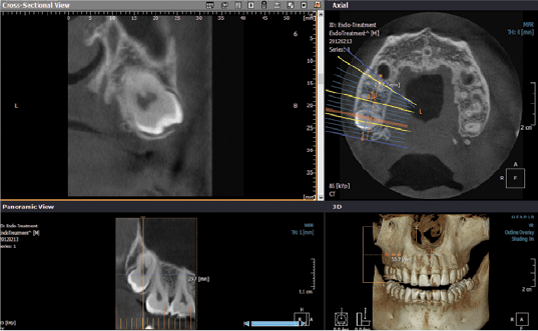

• Individuazione di fistole, sinusite mascellare odontogena e processi infiammatori periradicolari

Il Tomografo Cone Beam (detto anche CBCT Tomografia Computerizzata Cone Beam) è un macchinario in grado di ottenere immagini del massiccio facciale attraverso l’emissione di una dose molto bassa di raggi X, restituendo immagini 3D di altissima qualità delle ossa mascellari e dei denti.

La tecnologia della CBCT permette di ottenere immagini precise a dimensioni reali tridimensionali e ad alta risoluzione con tempi di scansione ridotti.